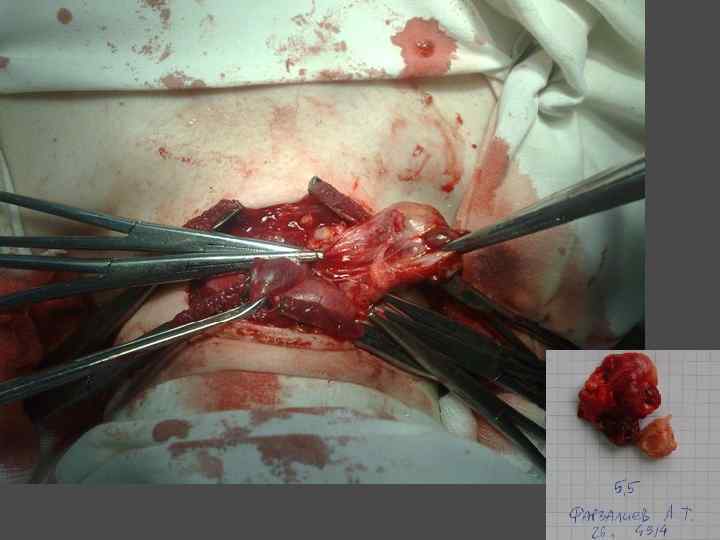

ЭКТОПИРОВАННАЯ В ТИМУС ПАРАЩИТОВИДНАЯ ЖЕЛЕЗА